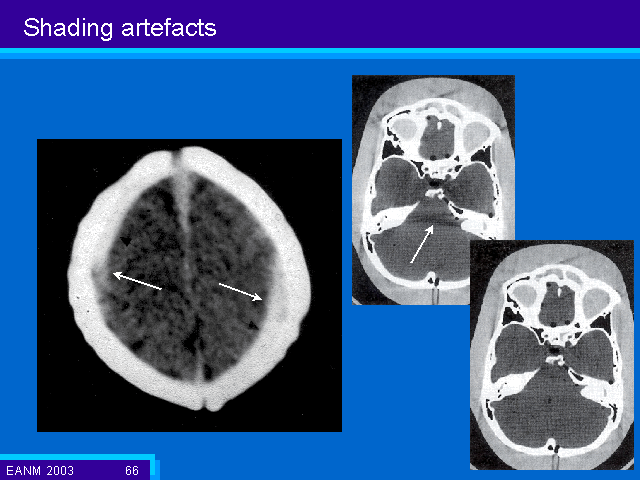

Slide 66 of 74